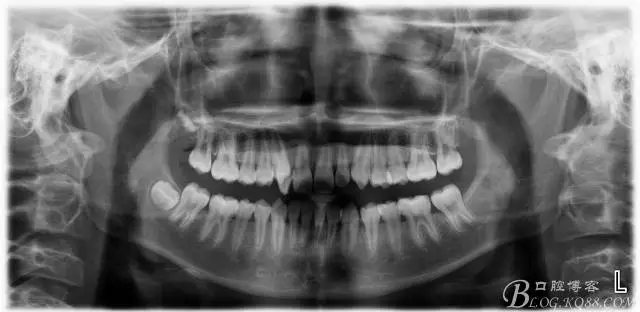

矯正過(guò)程中對(duì)牙周進(jìn)行了手術(shù)治療;